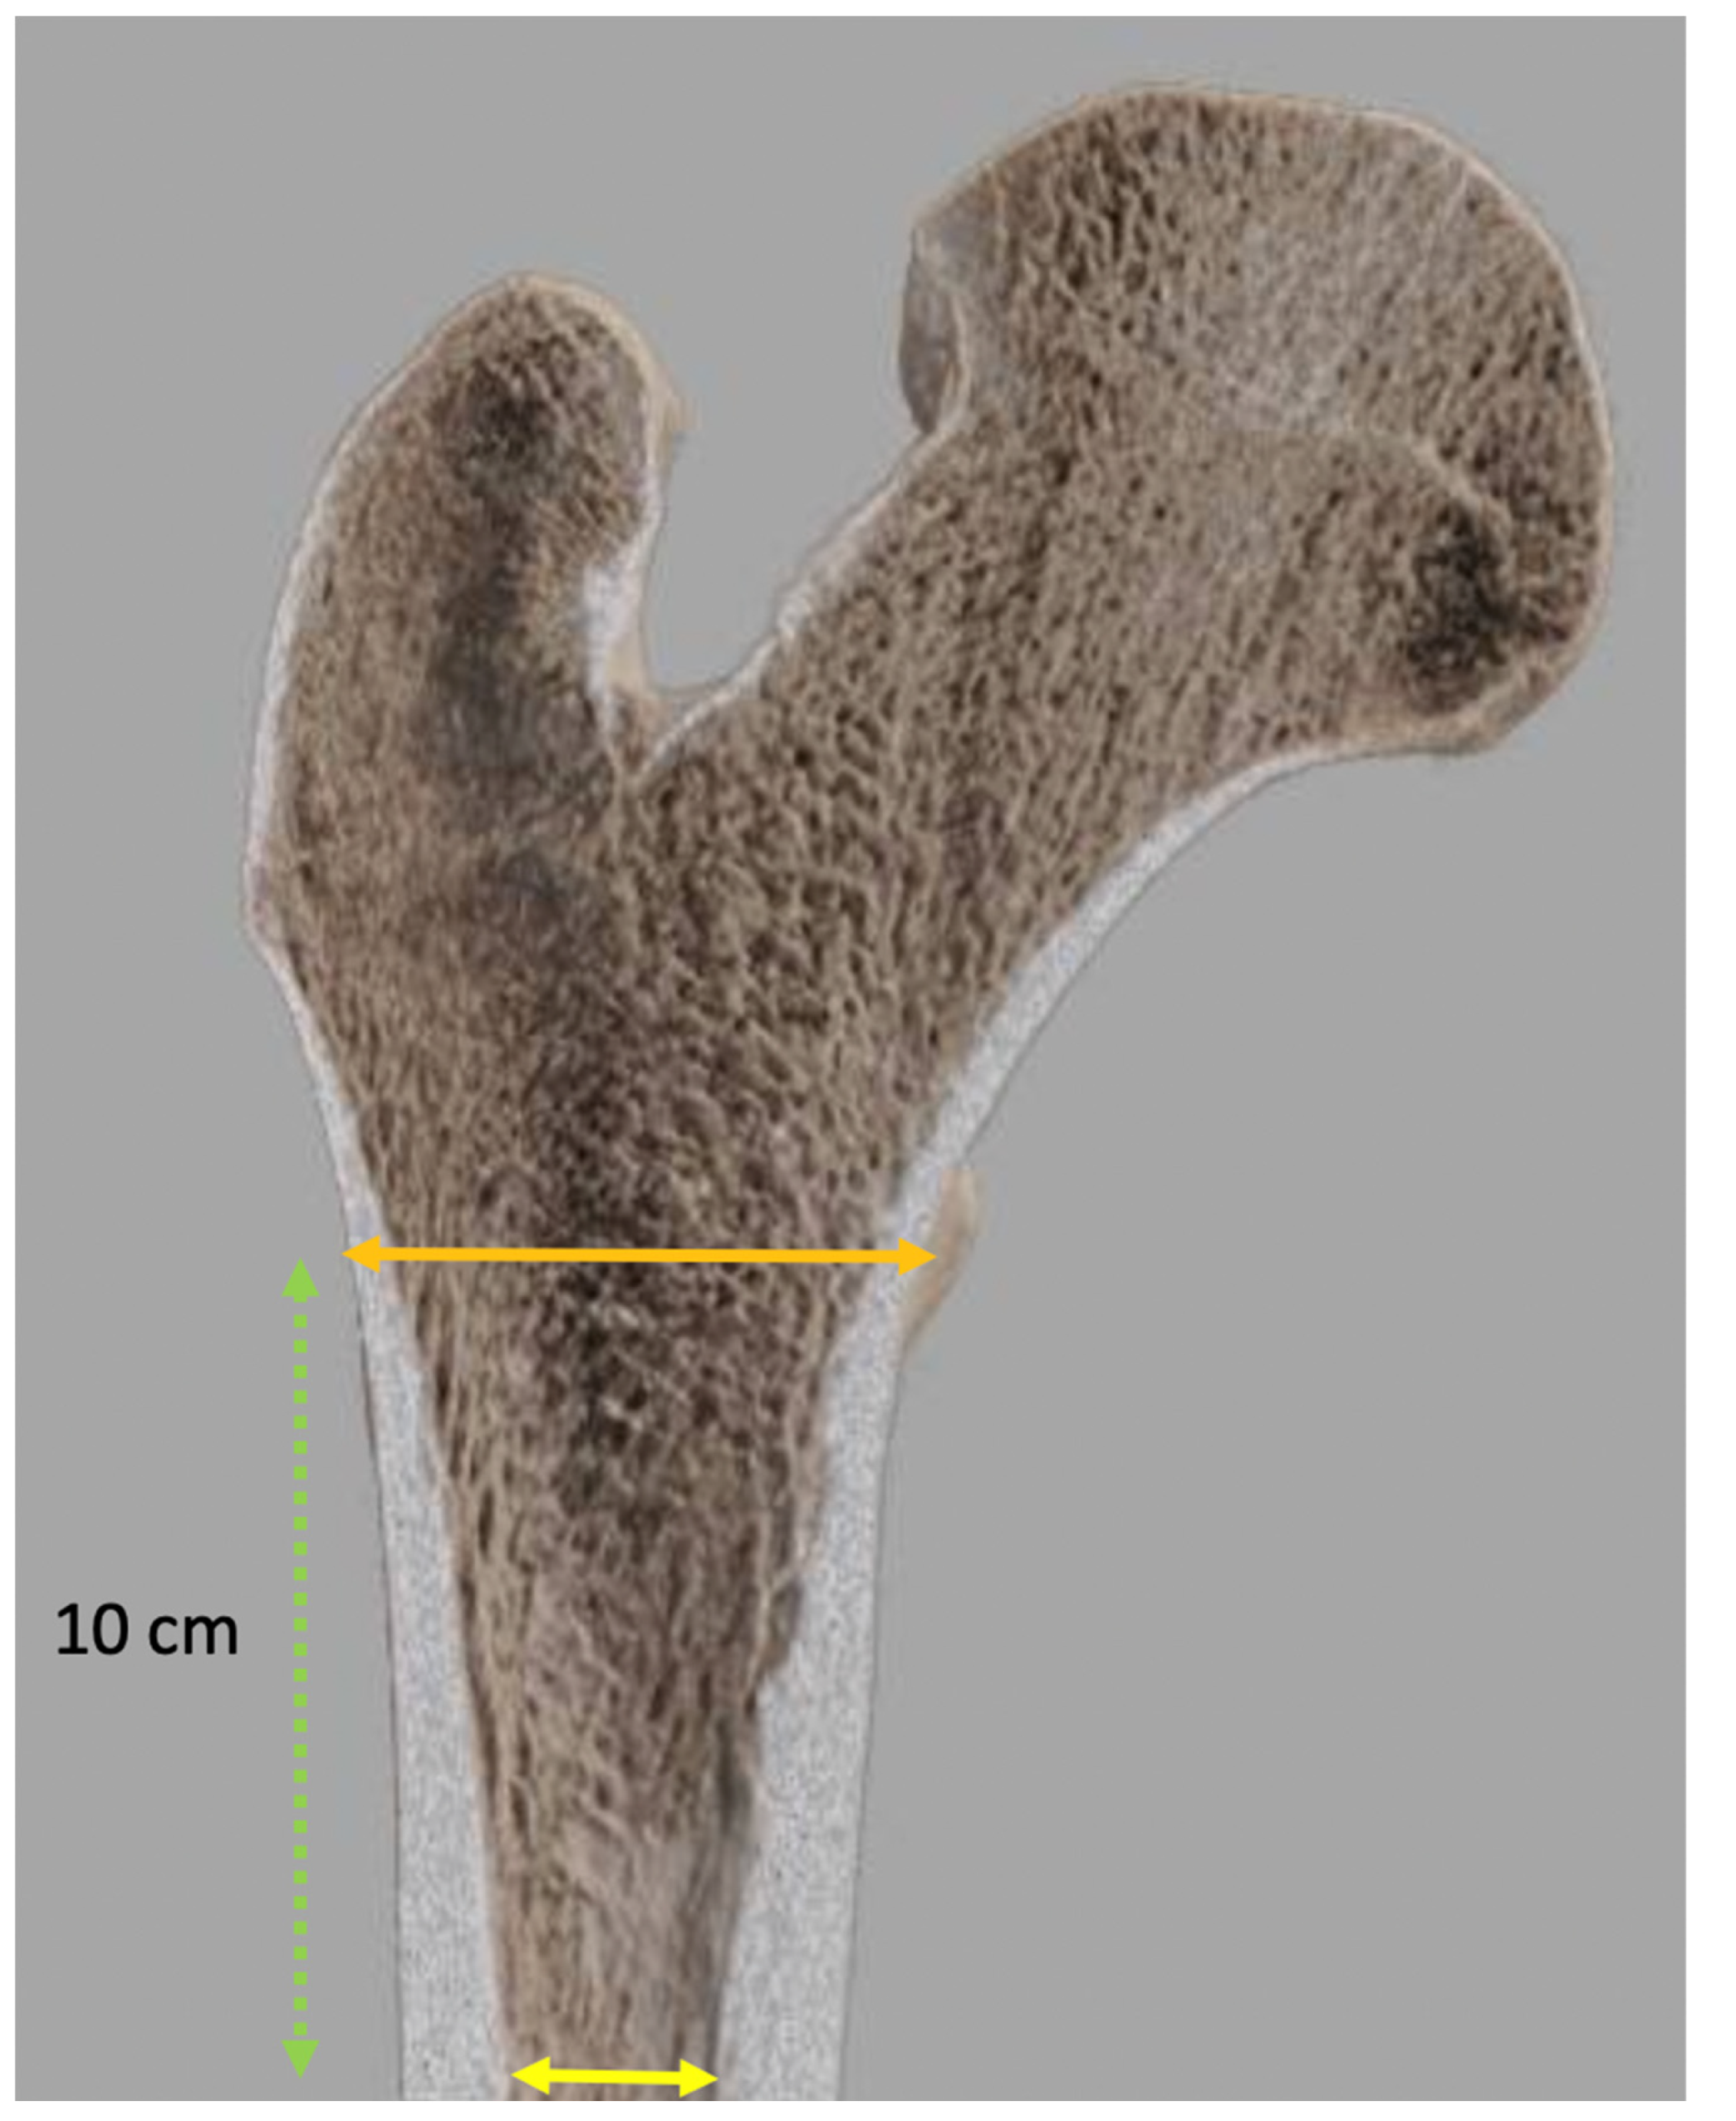

Femoral Stem Templating

- Dorr, L.D.; Faugere, M.C.; Mackel, A.M.; Gruen, T.A.; Bognar, B.; Malluche, H.H. Structural and Cellular Assessment of Bone Quality of Proximal Femur. Bone 1993, 14, 231–242. [Google Scholar] [CrossRef]

- Wilkerson, J.; Fernando, N.D. Classifications in Brief: The Dorr Classification of Femoral Bone. Clin. Orthop. Relat. Res. 2020, 478, 1939–1944. [Google Scholar] [CrossRef]

| Width of the endosteal diaphyseal and metaphyseal canal diaphysis | Size of the femoral component |

| Femoral offset determination | |

| Femoral neck resection length | Positioning of the femoral component |

| Cervico-diaphyseal angle | |

| Height and diameter of the femoral head |